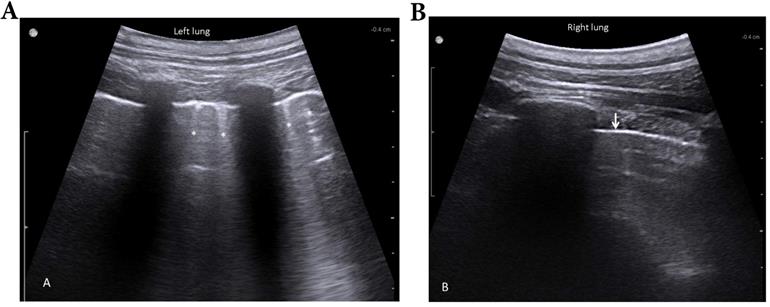

Color-coded duplex sonography of the pulmonary artery within the flooded lung revealed a strong oscillating flow pattern, which was found in all experiments (Fig. 5).

Figure 5

Duplex sonography imaging shows a biphasic oscillating flow in the pulmonary artery within the flooded lung (B, bronchus; R, ribs).

The oscillating flow in the pulmonary artery of the flooded lung is supportive evidence of the arrest of the pulmonary circulation. Similarly, oscillating flow patterns recorded in the extracranial cerebral arteries of brain-dead patients are considered to be conclusive signs of cerebral circulatory arrest [27,28]. The oscillating Doppler pattern is defined as a biphasic flow velocity spectrum with equivalent, opposing inflow and outflow components, such that the resulting time-averaged mean velocity in the evaluated vessel is zero [29].